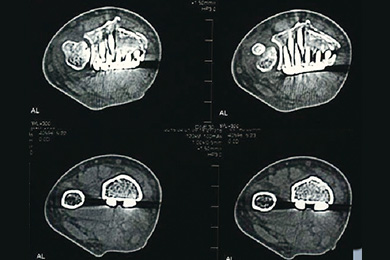

術後CT画像:どの位置でもハイブリッドロッキングプレートが骨に密着しています。